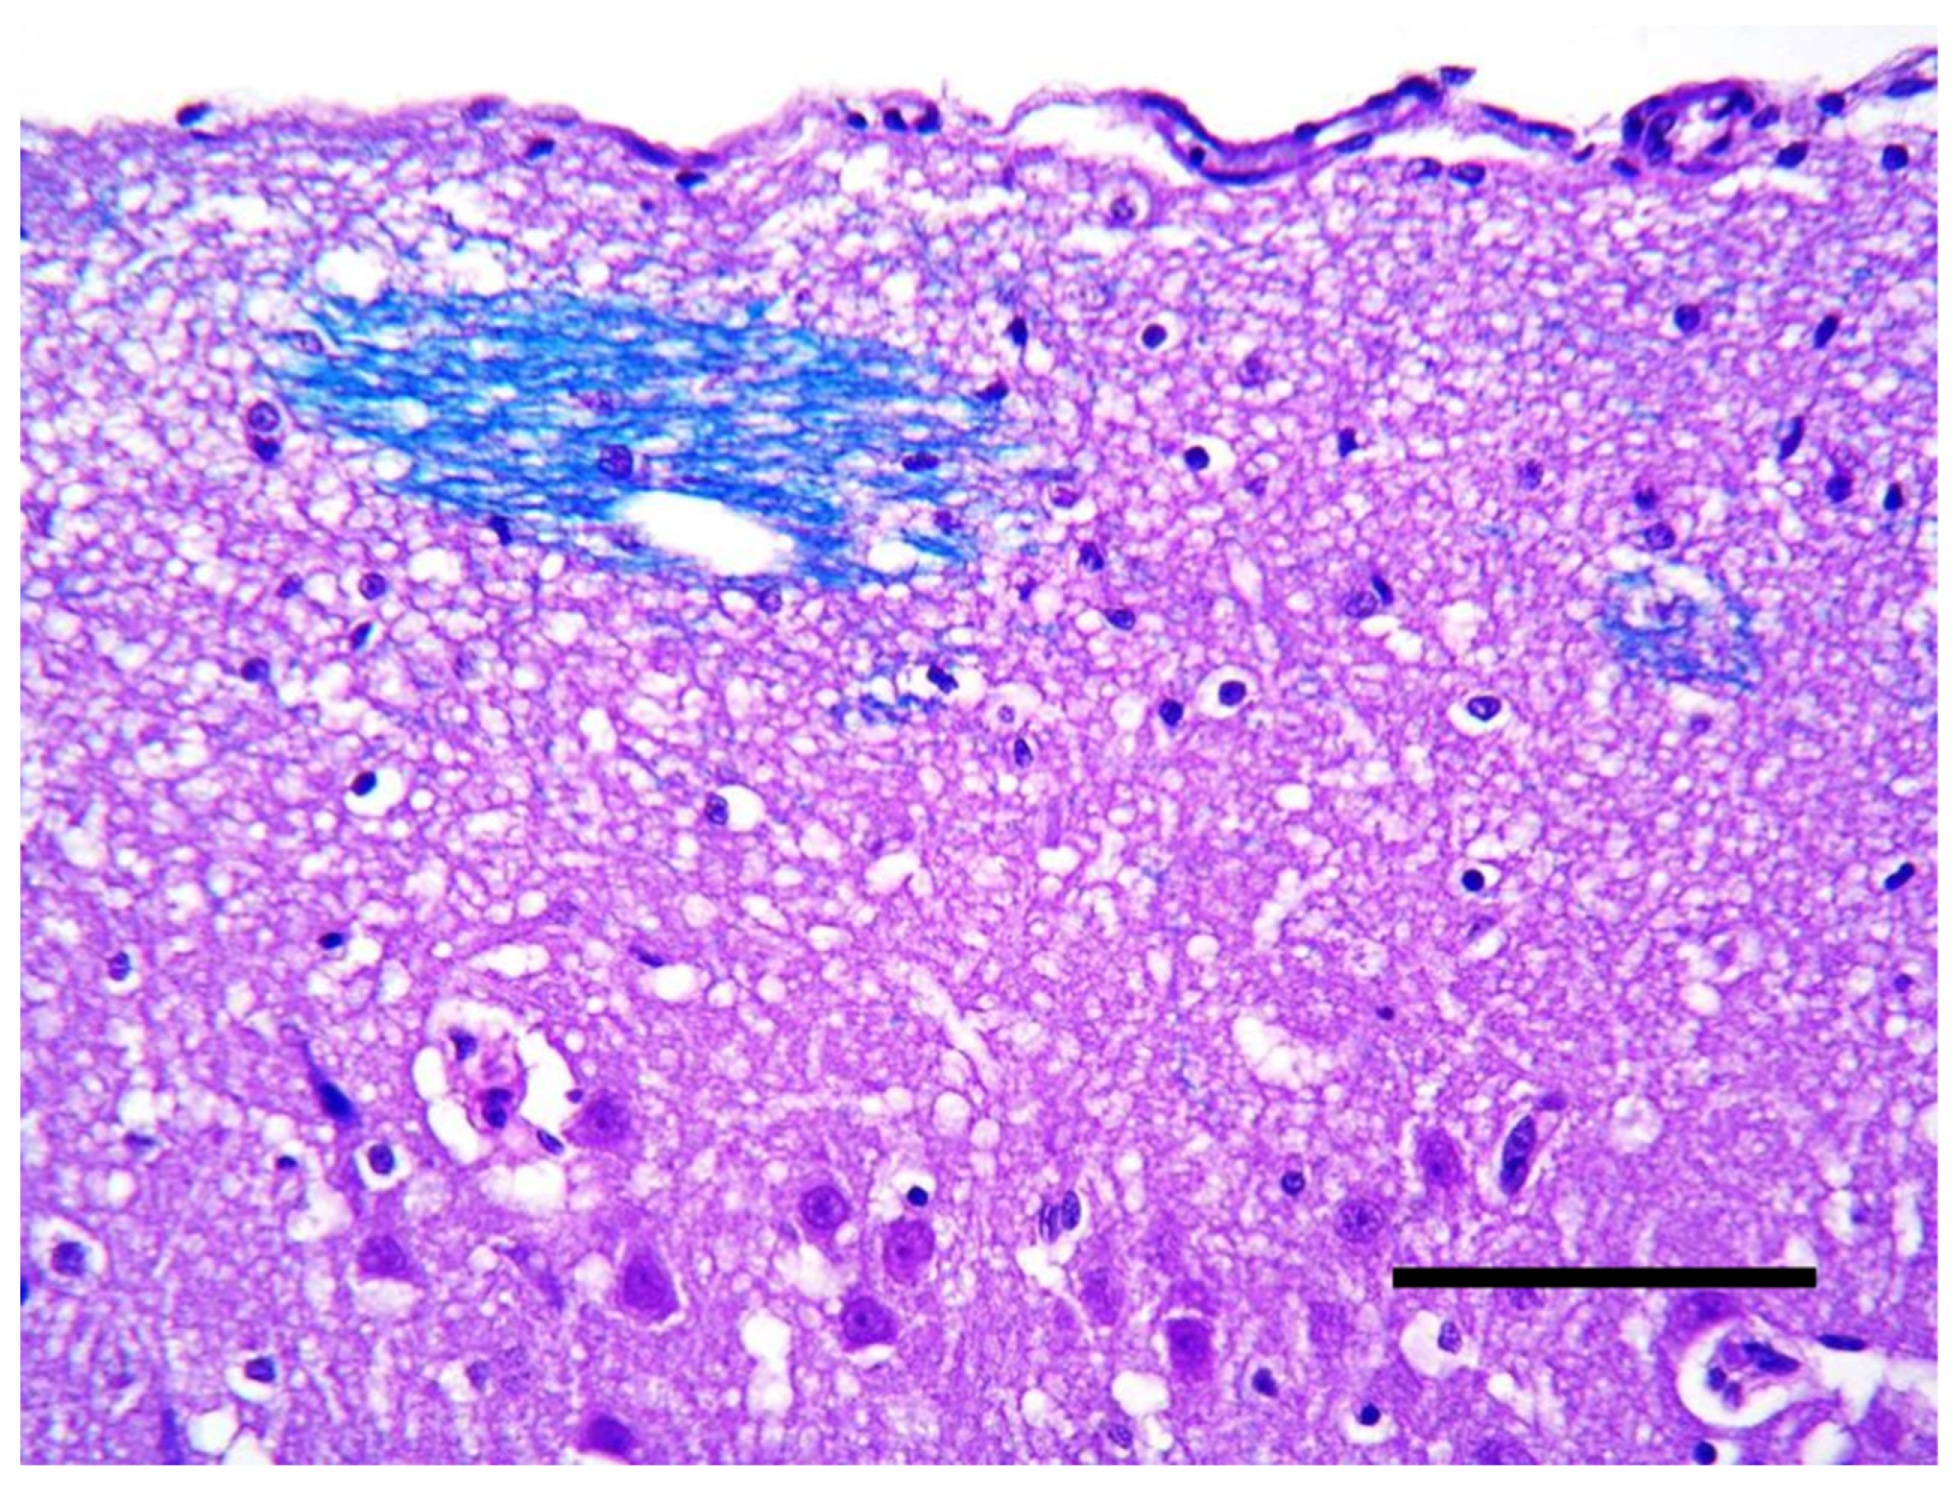

2. Case Description